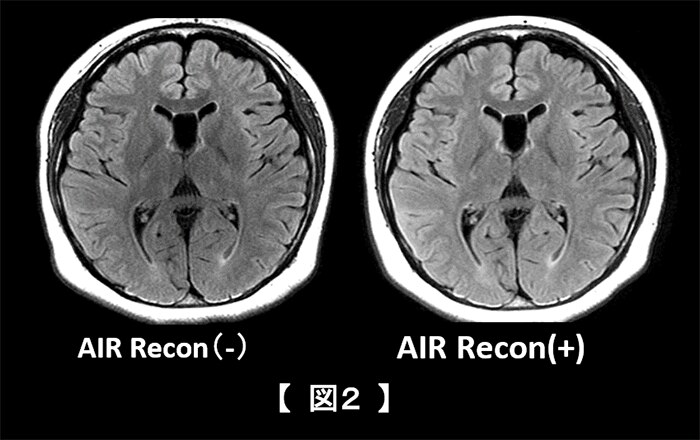

受信チャンネルの重みづけは感度の均一化にも一役買い、3T特有の頭部T1強調系の画像において有効に働いている。従来までの画像感度補正はPhased-array uniformity enhancement : PUREやsurface coil intensity correction : SCIC等により感度補正を行っていたが1)、AIR™ Reconによる感度均一化は従来の感度補正技術より効果が期待できる(図2)。